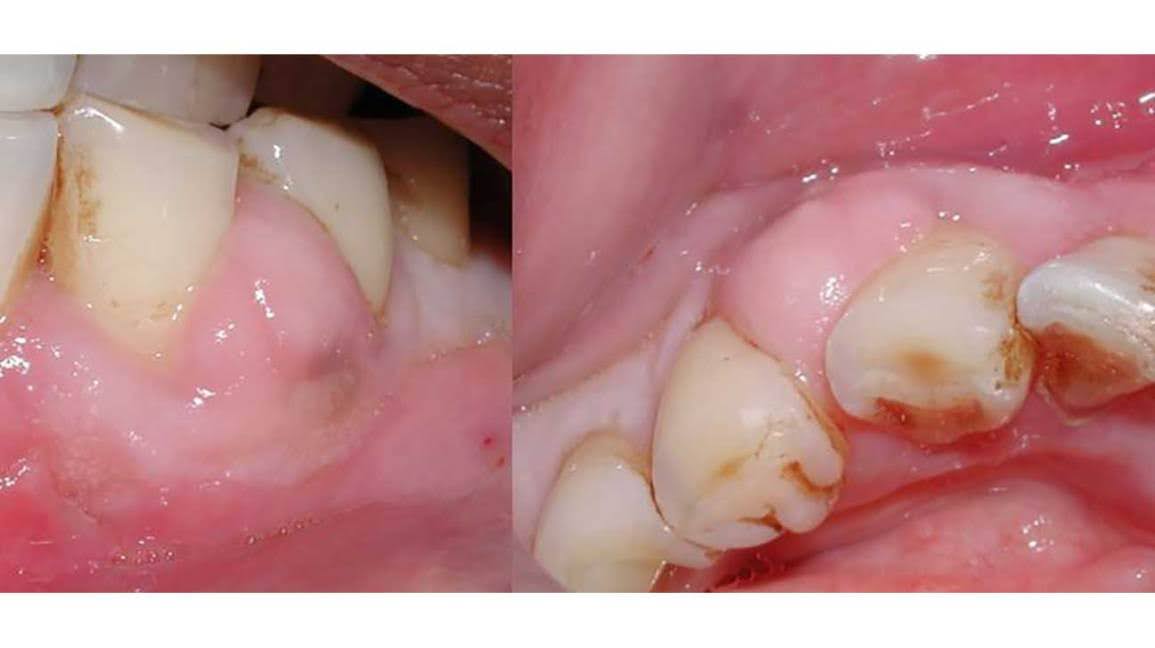

4. Infection or Abscess

A dental infection can weaken the bone and tissue surrounding a tooth, causing it to become loose.

This is a serious condition that requires prompt treatment.

5. Bone Loss in the Jaw

Bone loss can occur due to untreated gum disease or long-term missing teeth. When there isn’t enough bone to support the tooth, it may begin to loosen.

This process is often gradual but can become severe over time.